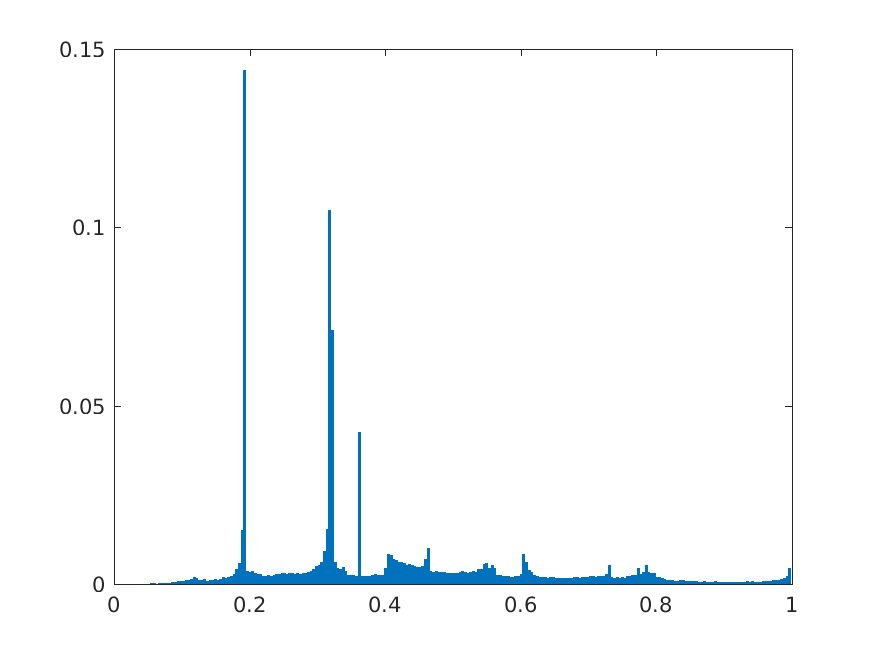

For all these experiments, we found that taking features from earlier layers compared to later layers improve accuracy by 2 to 4 percentage points. Shallow DCN features are often useful for detecting small objects in images [27]. Our findings are similar for chest X-Ray abnormality classification as well. As an example, we are showing the performance obtained by taking features from different layers of ResNet-152 model. The candidate layers are chosen from the 4th, 5th and final stage of the network based on what type of operations they perform. The chosen layers and their corresponding operations are listed in Table 3. The notation of the layers is based on the pre-trained model obtained from MatConvNet Pre-train Library. We trained five models to detect cardiomegaly using features from each of the layers and the average performance of these features in terms of accuracy, AUC, sensitivity, and specificity for Cardiomegaly detection are shown in Fig. 3. It can be observed that the performance of the final pooling layer (pool5) is degraded compared to the other layers in terms of accuracy, sensitivity and specificity. In particular features from residual connections (res4b35, res5c) and ReLU (res4b35x, res5cx) are considerably better with features from res4b35 providing highest accuracy. Similar observations are made for other ResNet variants, VGG nets and AlexNet.

8 Additional Examples of Localization

In this section we show more examples of localization. Few localization samples are shown in Fig. 11. It can be observed that, in the CXRs with Cardiomegaly (Fig. 11(a) and (b)) a fine localization around the heart is observed. In the normal CXRs (Fig. 11(c) and (d)) such localization is not observed. Rather the lowest probabilities are spread out in the CXR image. It is interesting to note that, the localization algorithm gets low probability where the heart is enlarged during cardiomegaly, but the proportion is small compared to the localization in other areas of normal CXRs. In order to observe the performance of the heat map we computed histograms of heat maps of each of the 100 CXRs in the test set for Cardiomegaly detection and average histograms are shown in Fig. 11(e) and (f) for CXRs with Cardiomegaly and normal CXRs, respectively. It is to be noted that, the histograms include both success and failure cases. It can be observed that, for CXRs with Cardiomegaly the classifier is highly sensitive toward Cardiomegaly detection even under occlusion. This indicates that, the classifier primarily looks for local features in a CXR instead of some feature that is spread out in the entire CXR. However, the classifier is not sensitive toward normal CXRs under occlusion. Rather, the probabilities are spread out in the probability spectrum. After that, we analyzed the failure cases where the classifier is unable to classify the image correctly. Two such examples of failure cases are shown in Fig. 12. The localized CXR shown in Fig. 12(a) contains Cardiomegaly whereas the classifier detects it as normal. However, the localization shows that it localizes around heart quite well despite the in accurate classification. On the other hand, Fig. 12(b) shows an example of normal image which has been classified as Cardiomegaly by the classifier. There is stronger localization around the hear that that is observed for normal images as in Fig. 11(c) and (d), however, like those images the localization is spread out.

In a similar fashion, additional localization results for Pulmonary Edema is shown in Fig. 13. In Fig. 13(a) and (b) localization of two examples of CXRs with Pulmonary Edema is shown. As stated earlier the classifier localizes in the lung region. This is not the case when normal images are used to localize Pulmonary Edema as seen in Fig. 13(c) and (d). The localizations are obtained in random dense locations such as the sternum or heart. Like the cardiomegaly case, the histogram averages for CXRs with pulmonary Edema (Fig. 13(e)) shows a sensitivity toward pulmonary edema detection while the normal CXRs shows a spread out detection. It is interesting to note that, in the histogram of normal images high probability (¿0.85) is non-existent, thus ensuring low false positive rate. In the test set none of the normal images have been diagnosed as Pulmonary Edema. The failure cases are shown in Fig. 12. These CXRs are with Pulmonary Edema. However, the localization algorithm shows that one of them localizes in lungs whereas the other one shows a localization pattern similar to that obtained in normal CXRs.